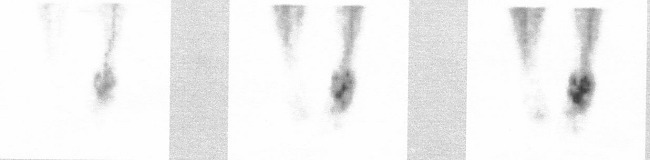

/Obrázek č.1:

Arteriální a blood pool fáze 3-fázové kostní scintigrafie (přední

projekce, zleva doprava sumace obrazů v 1.,2. a 3. min), hyperémie

levé dolní končetiny/